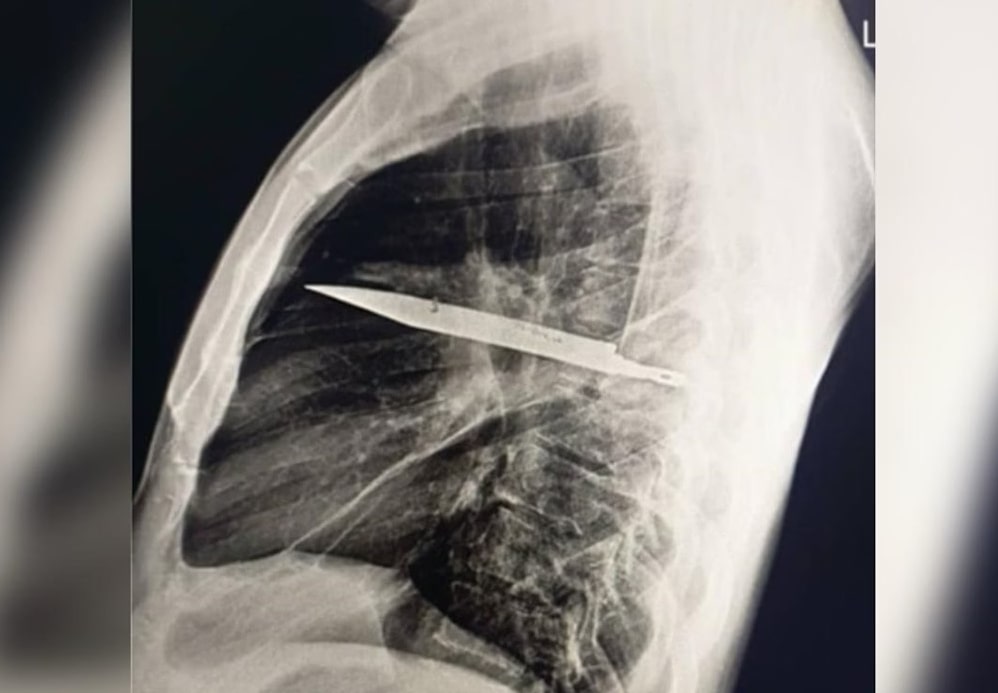

Surpresa no raio-x

O exame atual mostrou que uma lâmina estava presa ao lado direito do tórax, encostada à escápula. Apesar do tamanho, não atingiu órgãos vitais. Segundo os médicos, o acúmulo de pus foi causado pela presença do corpo estranho e por tecido danificado ao redor.